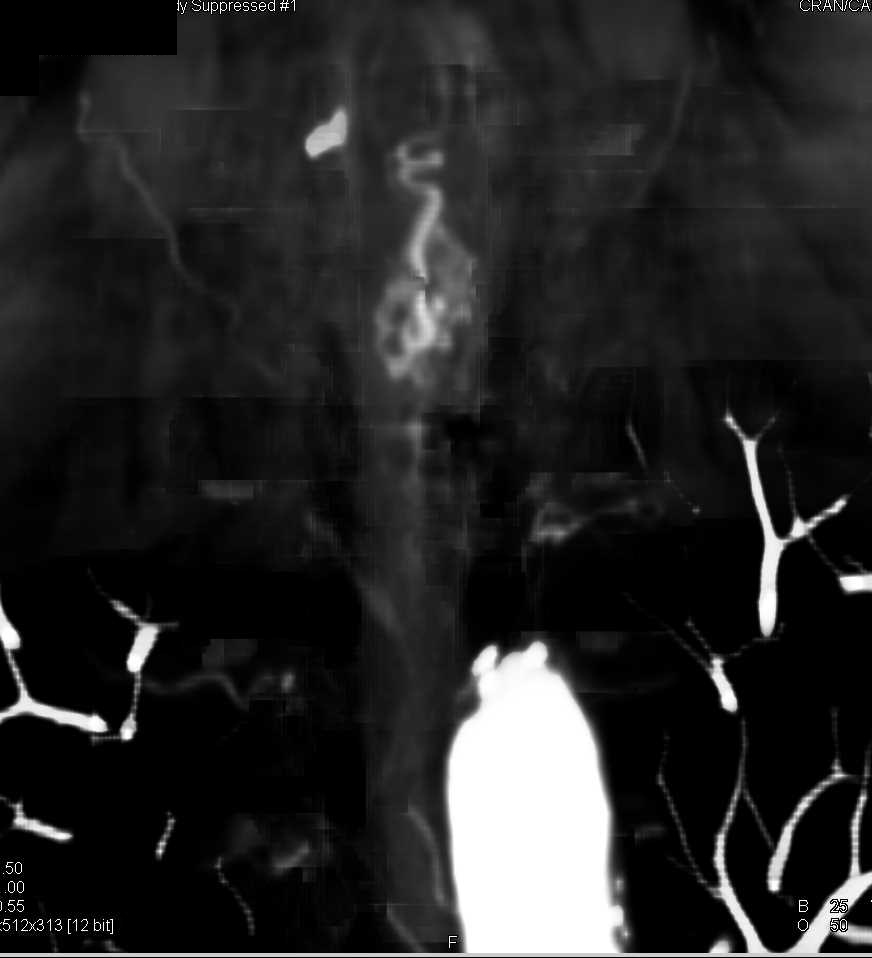

Left Renal Infarcts with Endovascular Stent